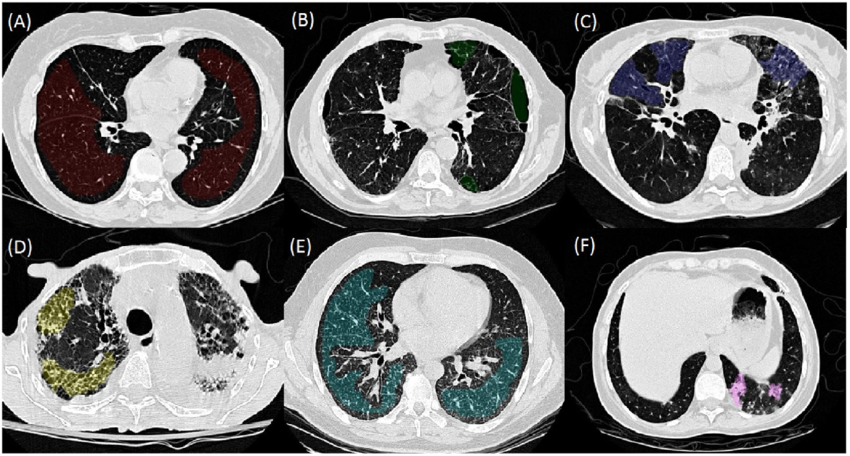

Tuy nhiên có một số dạng dữ liệu cực kì khó gán nhãn và đồi hỏi nhiều công sức cũng như kinh nghiệm của các chuyên gia. Ví dụ như ảnh y tế chẳng hạn, hãy thử nhìn bức ảnh sau xem. Nếu bạn có thể ngay lập tức gán nhãn các vùng ung thư trong phổi thì chắc hẳn bạn là một chuyên gia chẩn đoán hình ảnh hàng đầu rồi.